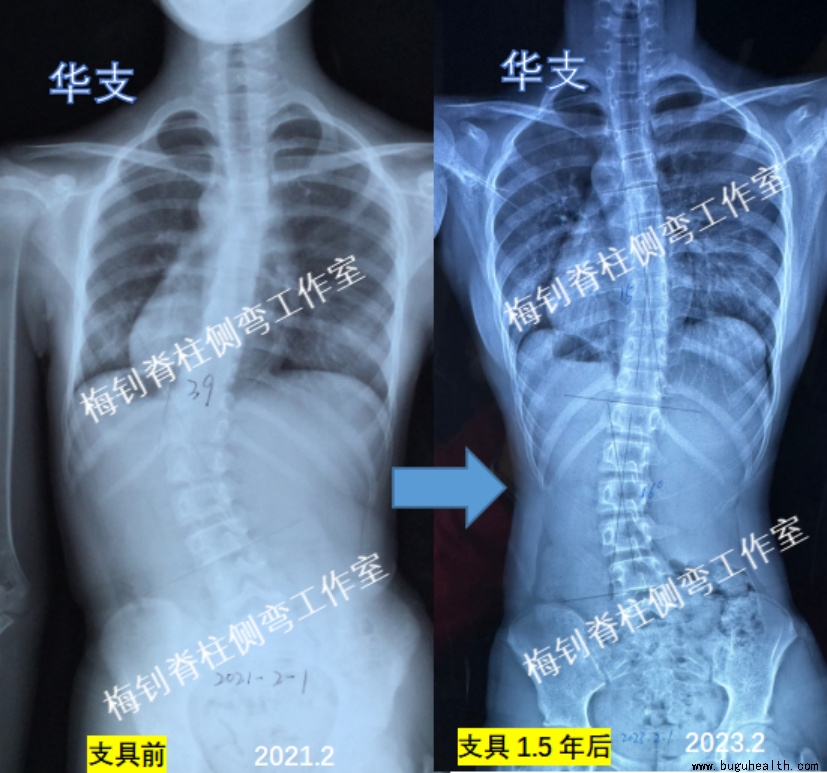

案例2

女孩,2021年2月发现侧弯,胸腰段向左侧凸39度。8月份开始支具干预。当时12周岁,刚来月经。

2023年2月,孩子穿戴支具1.5年,脱支具24小时拍片,主弯曲由39度降低为16度。期间,孩子身高增长8cm,体重增加8kg,更换支具1次。此外,体表的剃刀背也改善非常明显。针对目前脊柱弯曲的改变,后期干预的重点将从干预主弯曲向整体干预转变,期望孩子得到更好的康复。